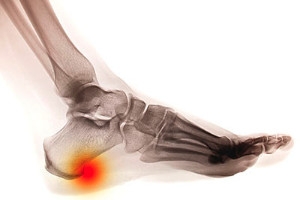

Because a woman's weight changes during pregnancy, more pressure is brought to bear on both the legs and the feet. This weight shift can cause two major foot problems: over-pronation, also known as flat feet, as well as edema, which is swelling of the feet. Over-pronation occurs when the arch of the foot flattens, causing the foot to roll inwards when the individual is walking, and can aggravate the plantar fascia tissues located along the bottom of the feet. If these tissues become inflamed, a pregnant woman can experience pain in the heel of the foot as well as severe foot pain while walking or standing. Swelling of the feet, or edema, often occurs in the later stages of pregnancy. It is caused by slow circulation and water retention, and may turn the feet a light purple color.